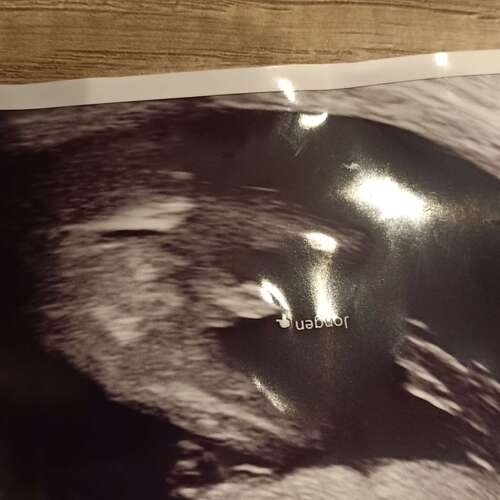

Hier 15 weken 6 dagen. Een jongetje, maar was met 13 weken echo ook al goed te zien🤣

Hier 15 weken 6 dagen. Een jongetje, maar was met 13 weken echo ook al goed ...

Zelfde echo